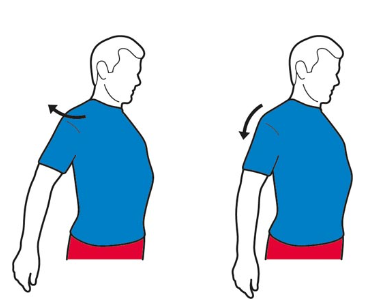

کشش شانه ها:

شانه ها را به آرامی به سمت عقب و روی هم فشار دهید و پنج ثانیه نگه دارید. شانه ها را به سمت پایین بکشید و پنج ثانیه نگه دارید. به آرامی و برای 10 بار تکرار کنید.